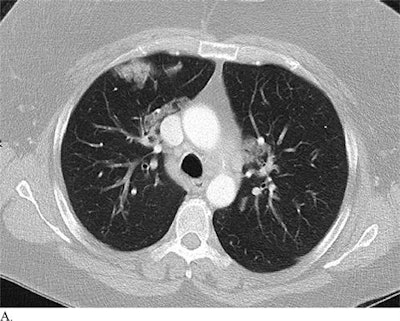

CT images of a patient with pneumonia misdiagnosed with COVID-19 (above) and a patient with COVID-19 misdiagnosed with non-COVID-19 pneumonia (below). All images courtesy of the RSNA.In the current study, Bai and colleagues evaluated the ability of radiologists to distinguish COVID-19 from other viruses on CT without knowledge of the patients' RT-PCR results or clinical information.

The researchers also listed several CT patterns that were much more common in patients with COVID-19 than in those without the disease: ground-glass opacity, peripheral distribution, vascular thickening, fine reticular opacity, and reverse halo sign.